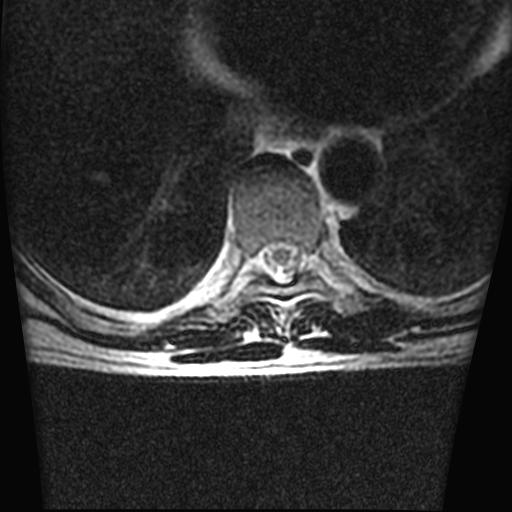

标题: MRI0985:胸椎.68岁男性,胸部疼痛,

68岁男性,胸部疼痛,不适。

胸7椎体楔状变形及信号异常,附件未见明显异常信号.椎间隙正常.未见软组织块影.考虑骨质疏松所致压缩性骨折可能大.

胸7椎体楔状变形及信号异常[t1t2 均为低信号],附件未见明显异常信号.椎间隙正常.未见软组织块影.考虑陈旧性压缩性骨折伴退变。

首先需除外单发成骨性转移瘤可能。